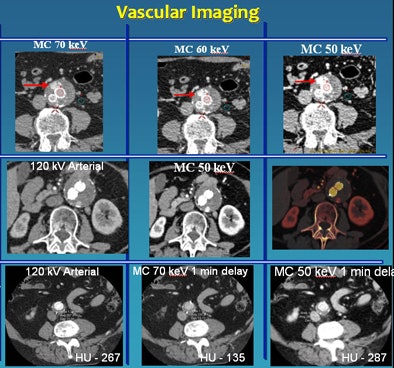

Among their strengths, low-kV scans are "especially popular for vascular imaging because one can exploit the k edge of iodine to gain more attenuation and, therefore, better image quality," Sahani said.

![]() |

| Low-kV imaging improves vascular imaging. Top, middle rows: Endoleak detection is easier on lower-kV images. The CT angiography study was acquired with only 40 mL of IV contrast. Bottom, on delayed-phase acquisition, 50-keV material composition (MC) image provides enhancement and attenuation values similar to arterial-phase imaging. |

The group has traditionally used a three-phase protocol for vascular imaging, but supported by low-kV imaging it's being abandoned in favor of a two-phase protocol that eliminates the unenhanced phase, he said.

In general, the group has found that 50 kV is optimal for vascular imaging, and 70 kV strikes a nice balance for a combination of vascular and solid visceral imaging, producing good image quality, Sahani said.